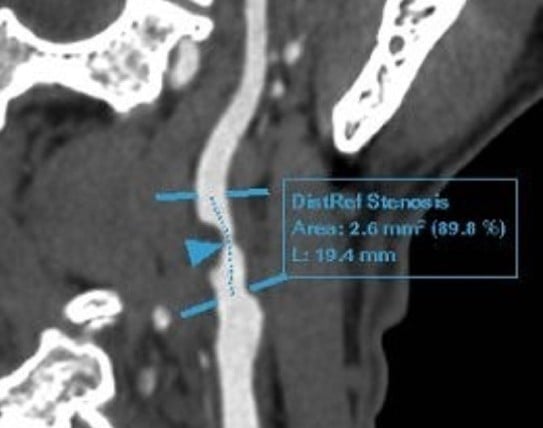

Az ultrahang- és agyi angiográfia eredményei azt mutatták, hogy D. úrnak a jobb oldali arteria carotis interna súlyos, 90%-os szűkülete volt vegyes ateroszklerotikus plakkok miatt, amit a bal oldali arteria carotis interna kismértékű disszekciója és egy kis aneurizma kísért. A plakkok az artériák több más szegmensére is átterjedtek, például a subclavia artériára és a kavernózus sinusra. A koszorúér CT angiográfia enyhe meszesedést mutatott ki, ami a koszorúér ágainak 30-40%-os szűkületét okozta.